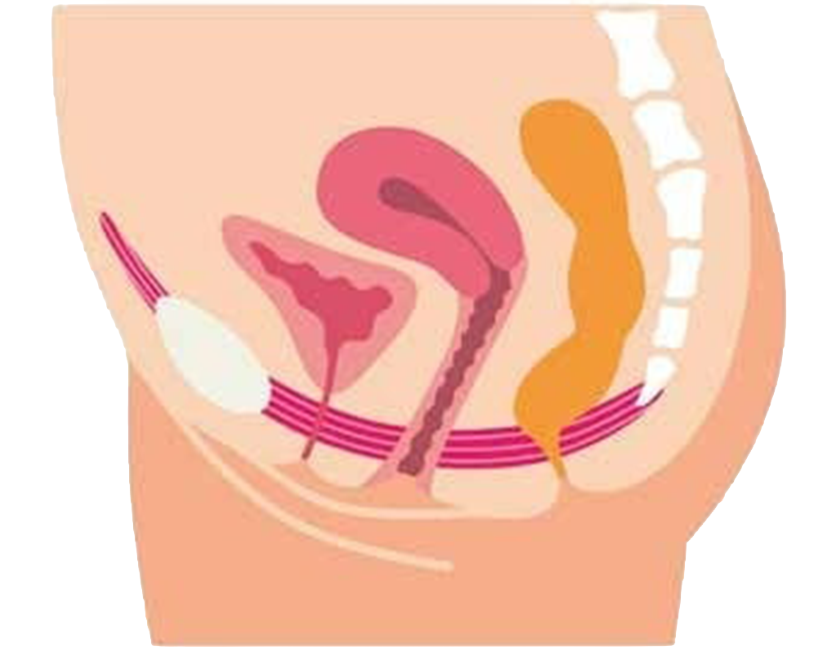

Sichere und schnelle Stärkung und Regeneration eines schwachen und dysfunktionalen Beckens in der ersten Zeit nach der Geburt (ab 7. Woche).

Verbesserung der Muskelkraft und -funktion, sowie Normalisierung neuronaler Signale helfen effektiv bei vielen Formen der Inkontinenz.

Durch eine verbesserte Durchblutung der gesamten Beckenregion und somit einer besseren Selbstregulation in diesem Bereich, können Wechseljahrsbeschwerden, das Lustempfinden und die Libido positiv beeinflusst werden.

Ob nach Prostata OP, errektiler Dysfunkton oder zur allgemeinen Potenzsteigerung ist ein trainierter und vitaler Beckenboden von grundlegender Bedeutung.

Ein funktionaler Beckenboden hat eine zentrale Rolle für die Stabilität der unteren Lendenwirbelsäule und verhilft zu einer besseren Körperhaltung. Zu schwache oder verkrampfte Gesäßmuskeln können Schmerzen verursachen, da durch diese viele Nerven (u.a. der Ischiasnerv) durchziehen und komprimiert werden können.